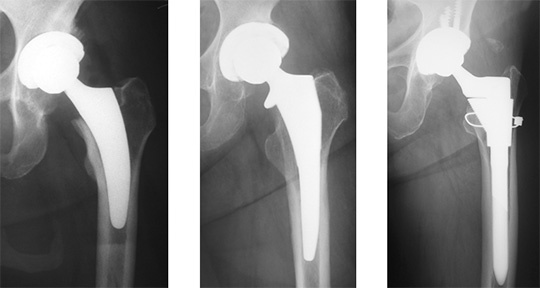

| 79歳女性 右変形性股関節 | 77歳女性 左変形性股関節 | |

| 術前 | 術前 | |

| 術前は、歩行時痛が著明である。 | 術前は、歩行時痛が著明で、 重度の歩容異常を認める。 |

|

| 術後1週 | 術後3週 | |

| 術後1週時には、痛みなく歩行が 安定している。 |

術後3週時には、軽度の歩容異常を 認めるが、痛みなく安定した歩行である。 今後更なる歩容改善が期待できる。 |